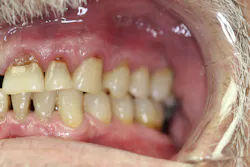

Upon receiving approval from his oncologist to commence with dental care three months later, his examination revealed the following (figures 1-5):

- Severe class III active periodontal disease

- Rampant, generalized cervical caries with some lesions quite extensive in nature

- Broken no. 8 (chief complaint)

- Broken/carious nos. 18, 19, and 30; caries on no. 2

- Generalized dry mouth with white patchy mucosa; he did have a complaint of having a “sticky mouth.” Note: When we took the photos, we had to put water in his mouth because it was so dry.

The genesis for his caries was evident–drug-induced dry mouth and time were the perfect storm for widespread infection that demanded immediate management. Suffice to say, my news to the patient was not welcome.